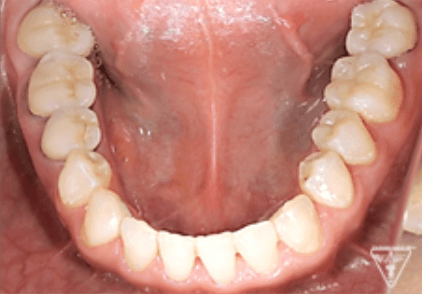

治療前

治療後